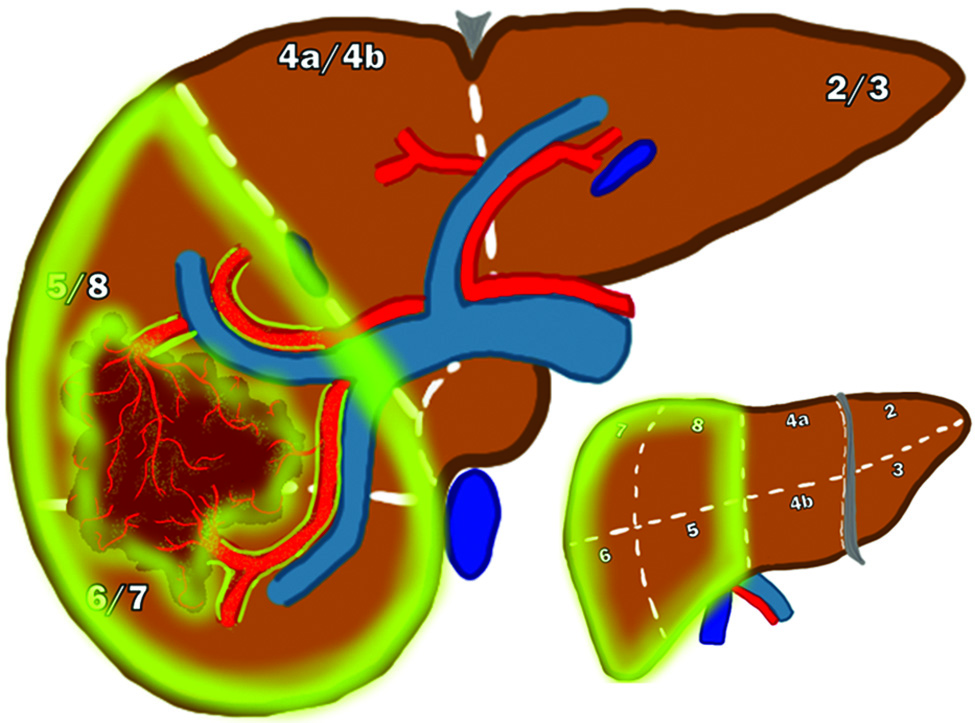

Un uomo di 65 anni con cirrosi da epatite C e un carcinoma epatocellulare (HCC) di 2,6 cm nel segmento 7.

(a) Immagine di Risonanza Magnetica (MRI) con soppressione del grasso in fase arteriosa T1 di una lesione epatica nel segmento 6. La punta di freccia bianca mostra il potenziamento del tumore.

(b, c) Immagini SPECT/CT fuse coronali con albumina macroaggregata di tecnezio-99m (Tc-99m MAA), con contorno del fegato normale (rosa), contorno dell'angiosoma di trattamento (blu) e contorno del tumore (rosso).

In b l'immagine è finestrata per mostrare l'assorbimento dell'angiosoma di trattamento (segmentectomia) rispetto all'assorbimento di fondo del fegato normale.

In c l'immagine è finestrata per mostrare che l'assorbimento del tumore è molto maggiore rispetto all'assorbimento dell'angiosoma di trattamento non tumorale (l'analisi SPECT/CT Tc-99 MAA ha mostrato un rapporto tumore-normale di ≥ 3).

È stata presa la decisione di somministrare 50 mCi con microsfere di vetro calibrate nella prima settimana (Giovedì) per un obiettivo di 400 Gy all'angiosoma.

(d) Immagini assiali fuse SPECT/CT di Bremsstrahlung di ittrio-90 della distribuzione di Y90 somministrata nel fegato. L'assorbimento corrisponde strettamente a quanto osservato durante la mappatura con SPECT/CT Tc-99 MAA.

(e) Contorni della SPECT/CT di Bremsstrahlung di Y90 per l'analisi dosimetrica, che dimostrano l'angiosoma di trattamento (viola scuro), il tumore (rosso) e il contorno del fegato normale (blu). La dose calcolata all'angiosoma di trattamento (segmentectomia) è stata di 433 Gy, e la dose effettiva di Y90 al tumore è stata di 1.062 Gy.

(f) MRI in fase arteriosa tardiva T1 con soppressione del grasso a 6 mesi dal trattamento che mostra (punta di freccia bianca) una risposta completa con alterazioni adiacenti dovute al trattamento.